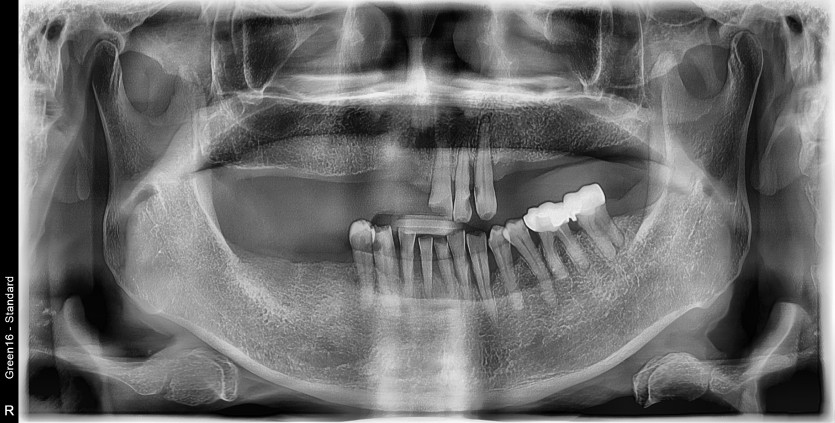

전체 임플란트 증례입니다.

15개의 임플란트로 완성하였습니다.